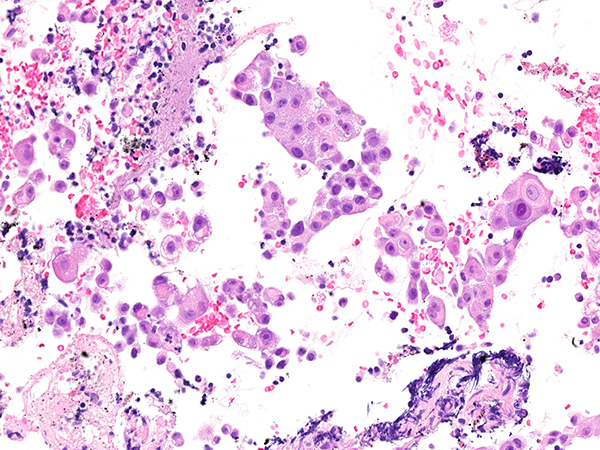

Clinical History: A 68-year-old man was found to have an incidental right lower lobe lung mass and hilar lymphadenopathy. A transbronchial biopsy was non-diagnostic and the patient subsequently had an EBUS scheduled for his 11R lymph node (Figure 1: H&E, Figure 2: TTF-1, Figure 3: napsin A, Figure 4: p40, Figure 5: alpha fetoprotein, Figure 6: HepPar1).

Hepatoid adenocarcinoma (HAC) of the lung is a rare aggressive primary lung neoplasm with aberrant hepatocellular differentiation, often with alpha-fetoprotein production. HAC can be seen as a primary tumor in other extrahepatic organs with the most common sites including gastric (63%), ovaries (10%), and lung (5%). Less common sites include gallbladder, pancreas, uterus, and testis. This tumor is seen in heavy smokers with a median age of 64 and has a preponderance of males (2.4 to 1) with a poor outcome. The medial overall survival is 11 months.

Histologically, HAC most often mimics hepatocellular carcinoma. The cells have eosinophilic cytoplasm, round nuclei, and have a meshwork of vascular spaces. The original description of this entity described it as a lung tumor with a component of hepatocellular adenocarcinoma type architecture seen in an otherwise typical acinar and/or papillary adenocarcinoma of the lung. Signet ring differentiation and neuroendocrine morphologies have also been described. These lesions were also originally found to secrete alpha fetoprotein (AFP); however, this is not a criterion for diagnosis and many cases do not secrete or stain for AFP. In patients that do have AFP production, the levels are often extremely high and can be utilized as a method to track recurrence and if a complete resection was achieved. For cases that are negative for AFP diagnosis can be made with the aid of hepatoid morphology together with positive HepPar 1 immunohistochemistry.

The hepatoid morphology can often be missed or not apparent, especially on small biopsies, and the first clue to this diagnosis is often a granular cytoplasmic staining with TTF-1. This should prompt staining for HepPar1 and AFP. The most important differential is a metastatic hepatocellular carcinoma. MOC31 and CK7 should be positive in HAC and negative in HCC. Polyclonal CEA will be positive in a non-canalicular pattern in HAC and positive in a canalicular pattern in metastatic HCC. This is an important differentiation to make as 15% of HCC cases metastasize and 47% of those mets are to the lung.

Take home messages for trainees: Hepatoid adenocarcinoma of the lung is a rare aggressive primary neoplasm of the lung that is histologically similar to metastatic hepatocellular carcinoma. The first clues are hepatoid morphology and/or granular cytoplasmic TTF-1 staining.